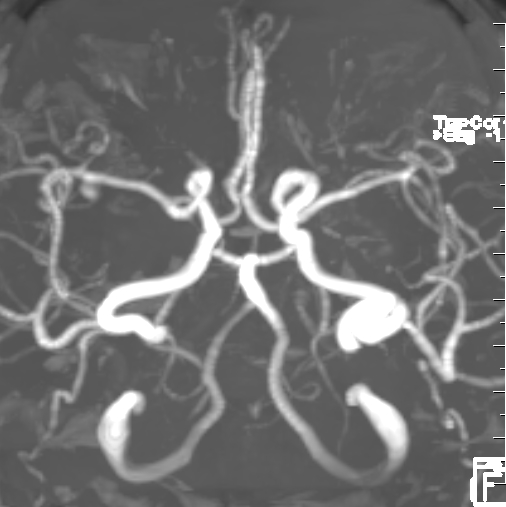

右侧大脑中动脉瘤,右侧椎动脉V2-V3粗细不均伴局部扩张

右侧大脑中动脉瘤,瘤颈处发出颞支,颈宽3.79mm,瘤高3.51mm,远近端载瘤动脉直径分别为2.43mm、2.52mm。

右侧椎动脉硬膜外V2、V3段梭形扩张,前向血流通畅。